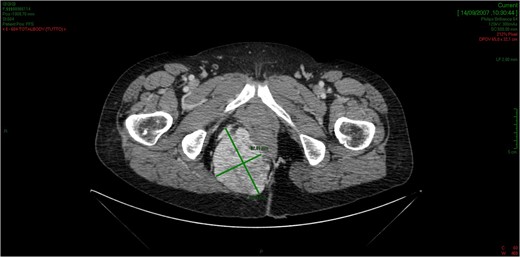

CT showed an hyperintense and inhomogeneous solid lesion taking up the right ischiorectal fossa (maximum diameter of about 10 cm), extended cranially until impressing the wall of the rectal ampulla, with no apparent infiltration (Figs 2 and 3). The lesion presented an intense contrast enhancement, sign of a rich vascularization (Fig. 4).

The CT scan demonstrates a solid neoformation in the right ischiorectal fossa.